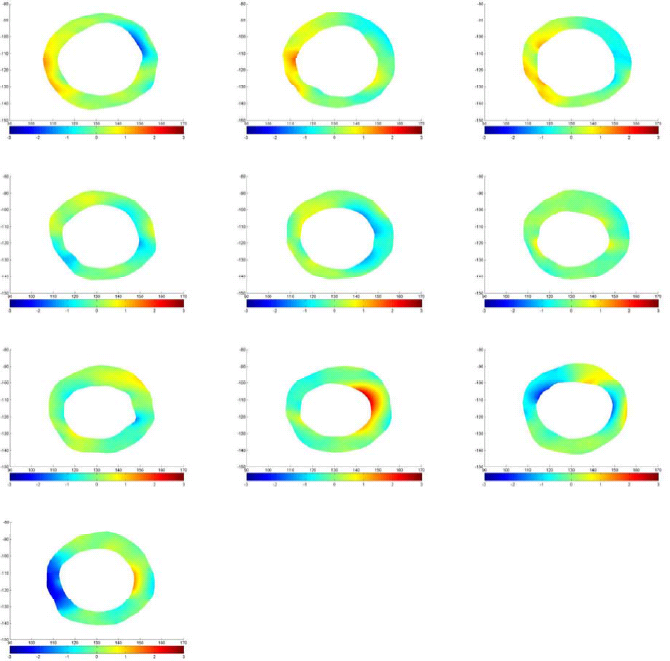

which in 2D case can be simplified because . Using this parameter we are able to monitor the changes in strain maps of heart muscle during deformation. Computing effective strain values for different slices of cardiac muscle, these values are used for comparison between healthy and MI subjects. Fig. 10 represent the results for first slice of healthy subjects, 18 and 25, and MI subject 23 during the cardiac cycle.

Fig. 11 shows the approximate infarct localization for the MI subject based on the comparison between normal and MI subjects’ effective strain during the cardiac cycle. Since the circulatory system of heart is determined very well, it is possible to make reliable conclusions about the problem that caused MI based on expert diagnosis and using these comparisons.